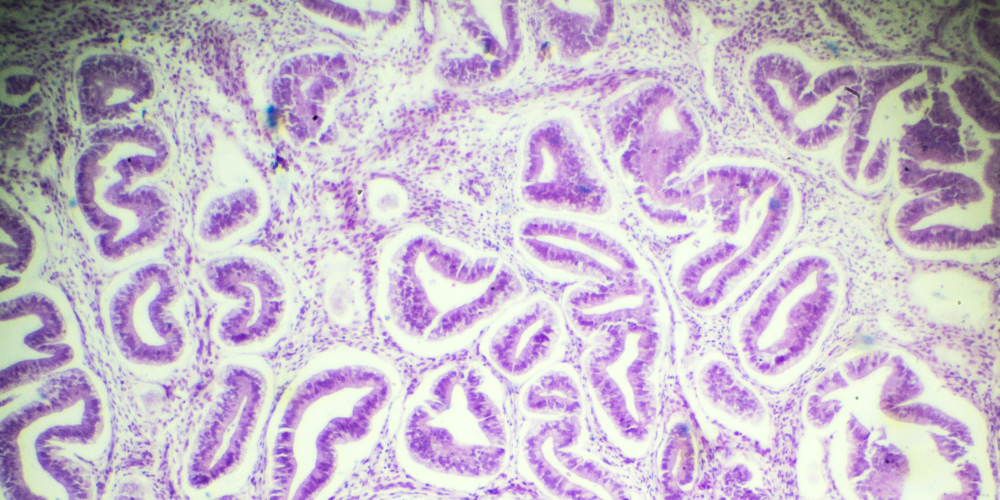

Adenomyosis is a condition in which the tissue that normally lines the uterus—known as the endometrium—grows into the muscular wall of the uterus. This abnormal growth often causes the uterus to become enlarged. Women affected by adenomyosis may experience heavier, longer periods accompanied by intense menstrual cramps. There may also be a persistent feeling of pelvic pressure or discomfort. Adenomyosis is typically diagnosed in women aged between 35 and 50 and can be confirmed using imaging techniques such as ultrasound or MRI.

Endometriosis, on the other hand, is characterised by the growth of endometrial-like tissue outside the uterus. This tissue can be found on the ovaries, fallopian tubes, and the lining of the pelvic cavity. Unlike adenomyosis, endometriosis does not cause the uterus to enlarge. Instead, it often leads to chronic pelvic pain, painful sexual intercourse, and complications such as infertility. In some cases, it can also cause pain during bowel movements or urination, particularly during menstruation. For more information, visit our dedicated Endometriosis Care page.

While both conditions involve the presence of endometrial tissue where it shouldn’t be, the key difference lies in location. Adenomyosis occurs within the uterine muscle wall, whereas endometriosis involves tissue outside the uterus altogether. This distinction influences how each condition presents and how it is treated.